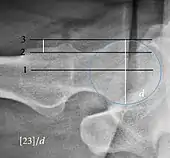

| Tönnis angle | ![]() |

Slope of the sourcil (the sclerotic weight-bearing portion of the acetabulum) | 0 to 10°

|

| Caput-sourcil angle[21] | ![]() |

Superior to the Tönnis angle in cases without joint space narrowing or subluxation.[21] The medial point of the sourcil is at the same height as the most superior point of caput femoris. | −6 to 12°[21]